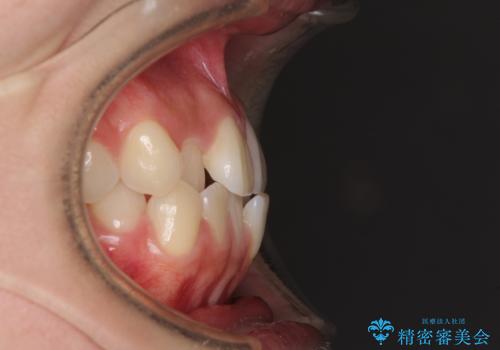

- 前歯のクロスバイトが気になり、インビザラインによる矯正治療を希望して来院された患者様です。

上顎側切歯(上の真ん中から2番目の歯)が舌側転位している場合、インビザラインでは仕上げきれないことが多く、更には無理して動かそうとすると歯髄壊死を起こすリスクが高いと言われています。

インビザラインで歯列を移動する前に、上顎前歯をワイヤー矯正で整え、その後上下歯列をインビザラインにて矯正治療を行うこととしました。

舌側転位している側切歯特有の、切縁の位置が不揃いであったり、根元が内側に引っ込んだ状態であったりという、インビザライン独特の仕上がりになることなく、きれいに整った歯列とすることができました。